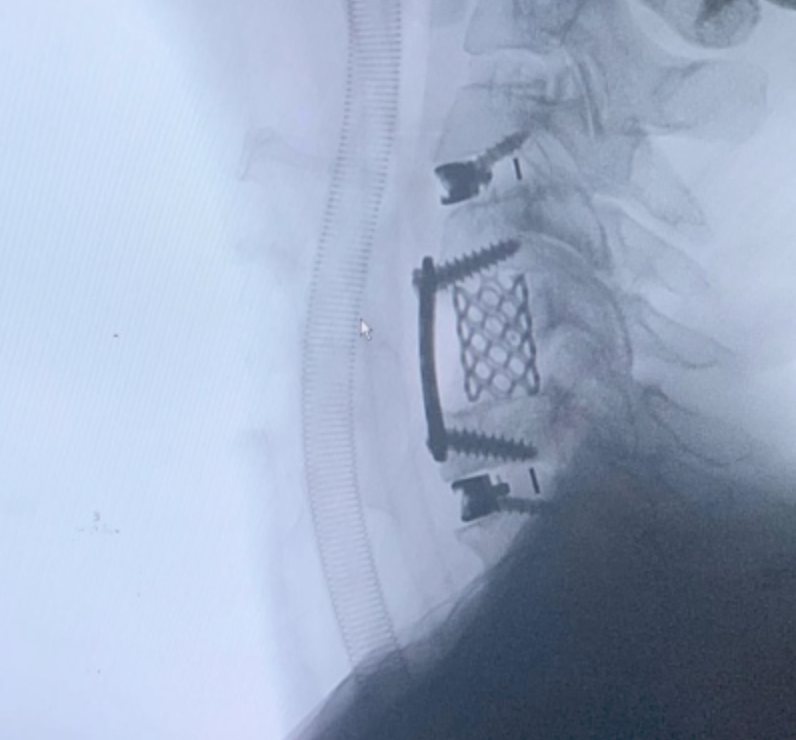

CIRUGIAS

RESULTADOS